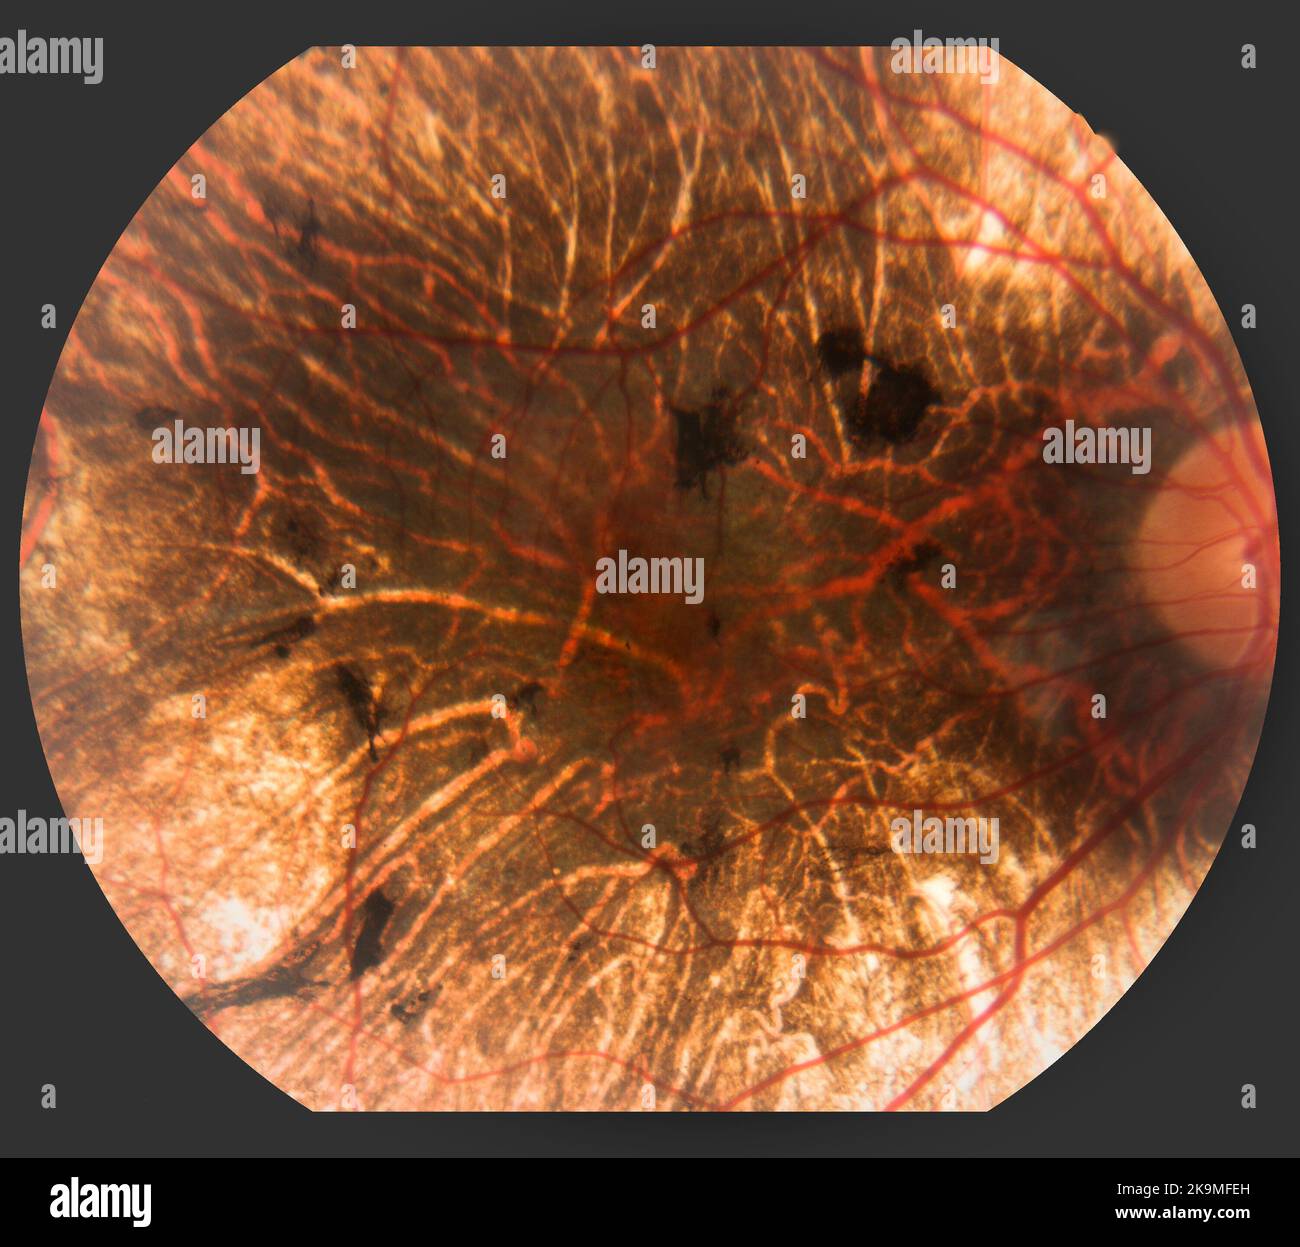

Diabetic Retinopathy Stock Photohttps://www.alamy.com/image-license-details/?v=1https://www.alamy.com/stock-photo-diabetic-retinopathy-134944962.html

Diabetic Retinopathy Stock Photohttps://www.alamy.com/image-license-details/?v=1https://www.alamy.com/stock-photo-diabetic-retinopathy-134944962.htmlRMHRF7JX–Diabetic Retinopathy